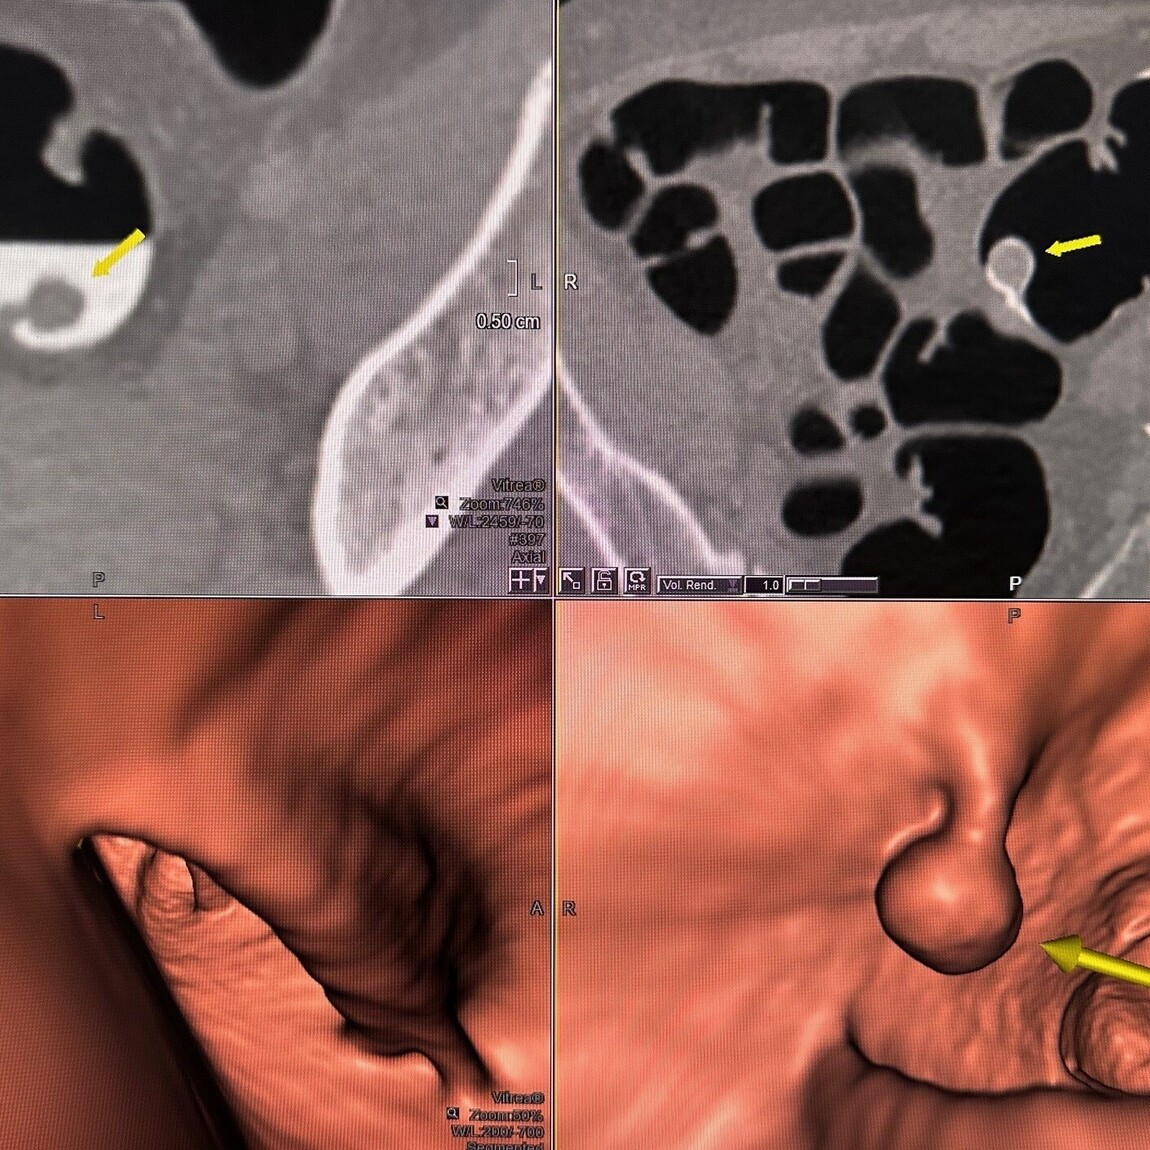

14mm diameter stalked polyp in patient with no symptoms and FIT test negative. CT colonography has identified the polyp using an endoluminal display

CT Colonography

The source CT image display with the polyp surrounded by tagged ‘white’ fluid